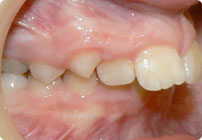

Galería

Femenino

Antes

Despues

Caso: 19 años

Adulto: Clase III

Mordida Abierta Anterior

Mordida Cruzada Anterior y Posterior

Endo necesitado para #19

Extract U5’s, LR4, LL6

6 alambres superiores

5 alambres inferiores

Elásticos Clase III 2oz. TP Verde

Retenedores: Interior Fijo de TMA y Hawley en superior

Tiempo de tratamiento: 21 Visitas